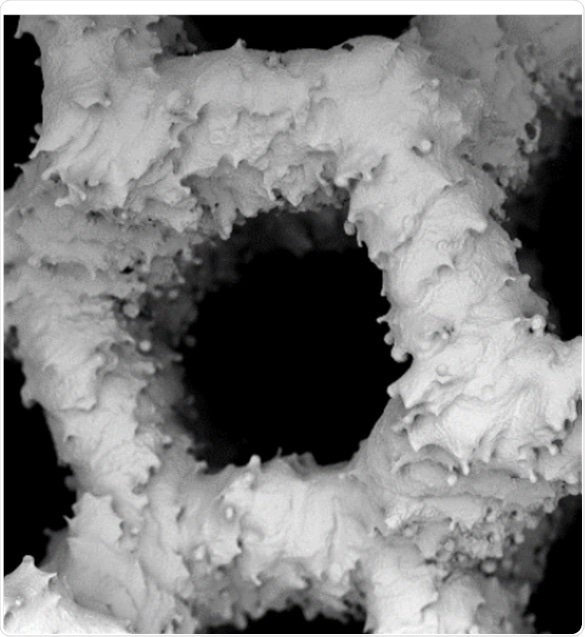

It is a big challenge to treat bone lesions caused by tumors, diseases, or trauma. Hence, Bone lesion treatment is a key subject of interest in orthopedic research. In a 2016 study led by a laboratory in Germany, bone lesion treatment with allografts1, which are tissues obtained from the patient’s own body, was compared with the treatment involving synthetic or processed xenogeneic bone grafts, which are tissues obtained from another person.

The laboratory used a SEM for this comparison, wherein the growth of human osteoblast (bone matrix cells) on BioOss, a human-like synthetic bone matrix, and on allogeneic bones after 1 week and then 3 weeks of culture, were compared. These images help concluding that the performance of the two materials is equal and confirm the efficiency of highly-processed synthetic grafts.

examples of SEM of human osteoblasts seeded on cancellous bone

Figure 1. Top row: examples of SEM of human osteoblasts seeded on cancellous bone (ACB) after 1 week of cultivation, showing embedded cells in a bone typical extracellular matrix (image magnification 555x and 1300x as indicated). Lower row: After 3 weeks of cultivation an extensive growth of the osteoblasts could be observed on the surface on BioOss® (image magnification 600x and 2840x as indicated). Images adapted1.